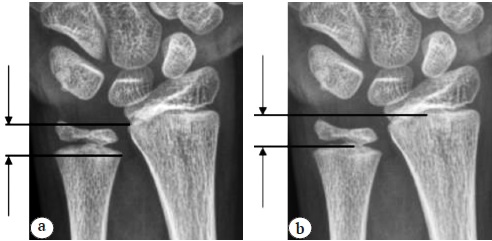

An X-ray functional study (radiography in the site of the ulnar head dislocation) enabled analysis of the change in the position of the ulna in the case of a clinically detectable subluxation/dislocation of the ulnar head, whereas on standard radiographs in the lateral projection, we did not reveal significant changes in the radioulnar distance in the affected limb (Fig. 9).

Fig. 9. X-ray of the wrist joint of a 13-year-old patient with a diagnosis of posttraumatic dislocation of the ulnar head. Instability of the distal radioulnar joint: a — lateral projection; b — X-ray functional examination in the position of dislocation of the head of the ulna (volar type)